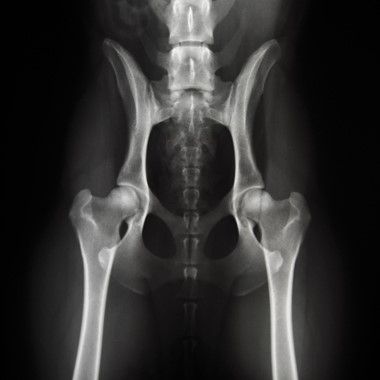

hüftgelenkdysplasie

Hüftgelenksdysplasie

Das HD-Röntgen ist ein wichtiges Verfahren, um Veränderungen der Hüftgelenke zu erkennen.